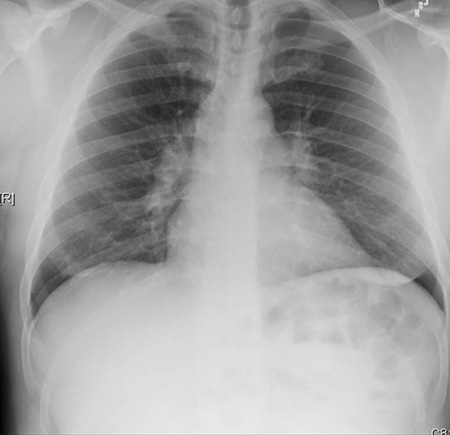

Chest x-ray

A chest x-ray should be obtained early in the evaluation of chronic cough.[38] Although it is not diagnostic of the most common causes, findings may quickly divert the evaluation to causes of greater gravity, such as structural lung diseases. These include lung cancer, pulmonary fibrosis, tuberculosis, bronchiectasis, pneumonia, aspiration, and sarcoidosis.[Figure caption and citation for the preceding image starts]: Chest x-ray showing hyperinflation in a patient with COPD. The hyperinflation is caused by the emphysema component of COPD, rather than the chronic bronchitis that underlies symptoms of coughFrom the personal collection of Dr M. A. Sharifabadand, SUNY at Stony Brook School of Medicine, Department of Pulmonary and Critical Care Medicine, Mineola, New York and Dr J. P. Parsons, The Ohio State University Medical Center, Columbus; used with permission [Citation ends].com.bmj.content.model.assessment.Caption@65a65855[Figure caption and citation for the preceding image starts]: Chest x-ray showing multiple miliary lung metastases (arrows). The primary tumour was a thyroid carcinomaE. Dick, Student BMJ. 2001;9:10-12 [Citation ends].com.bmj.content.model.assessment.Caption@25657fee[Figure caption and citation for the preceding image starts]: Chest x-ray showing left hilar carcinoma (arrow)From: E. Dick, Student BMJ. 2000;8:358-360 [Citation ends].com.bmj.content.model.assessment.Caption@567b9fef[Figure caption and citation for the preceding image starts]: Chest x-ray showing a cavitating right hilar carcinoma (arrow)E. Dick, Student BMJ. 2001;9:10-12 [Citation ends].com.bmj.content.model.assessment.Caption@3d6fa55[Figure caption and citation for the preceding image starts]: Chest x-ray in a patient with bronchogenic carcinoma showing a left-sided pleural effusionFrom: R. Thakkar, Student BMJ. 2001;9:458 [Citation ends].com.bmj.content.model.assessment.Caption@5b46acec[Figure caption and citation for the preceding image starts]: Chest x-ray showing interstitial fibrosis in a patient with amiodarone pulmonary toxicityFrom the personal collection of Dr A. Pataka and Professor P. Argyropoulou, Aristotle University, Thessaloniki, Greece; used with permission [Citation ends].com.bmj.content.model.assessment.Caption@2c3c94b0[Figure caption and citation for the preceding image starts]: Chest x-ray showing pulmonary tuberculosis with cavitationFrom the personal collection of Dr M. Narita, Department of Pulmonary and Critical Care Medicine, University of Washington [Citation ends].com.bmj.content.model.assessment.Caption@3dd7f84b[Figure caption and citation for the preceding image starts]: Chest x-ray showing multiple discrete nodules throughout both lungs (one of which is circled) in a patient with miliary tuberculosisE. Dick, Student BMJ. 2001;9:10-12 [Citation ends].com.bmj.content.model.assessment.Caption@23fa6365[Figure caption and citation for the preceding image starts]: Chest x-ray with lack of normal tapering producing a tram line in a patient with bronchiectasisFrom the personal collection of Dr S.M. Bhorade, University of Chicago Medical Center; used with permission [Citation ends].com.bmj.content.model.assessment.Caption@36b415f2[Figure caption and citation for the preceding image starts]: Chest x-ray with dilated and thickened airways in a patient with bronchiectasisFrom the personal collection of Dr S.M. Bhorade, University of Chicago Medical Center; used with permission [Citation ends].com.bmj.content.model.assessment.Caption@78e208fa[Figure caption and citation for the preceding image starts]: Chest x-ray showing increased opacification of the right perihilar region and superior segment of the right lower and upper lobes consistent with worsening aspiration pneumoniaFrom the personal collection of Dr R. Kanner, University of Utah School of Medicine [Citation ends].com.bmj.content.model.assessment.Caption@71be2c1f[Figure caption and citation for the preceding image starts]: Portable chest x-ray with bibasilar opacities, worse on the right than the left, in a patient with hospital-acquired pneumoniaFrom the personal collection of Dr F. W. Arnold, Division of Infectious Diseases, Department of Medicine, University of Louisville School of Medicine [Citation ends].com.bmj.content.model.assessment.Caption@2c704497[Figure caption and citation for the preceding image starts]: Chest x-ray showing early ill-defined opacities of the right upper lobe above the minor fissure consistent with early changes of aspiration pneumoniaFrom the personal collection of Dr R. Kanner, University of Utah School of Medicine [Citation ends].com.bmj.content.model.assessment.Caption@23fa54d0[Figure caption and citation for the preceding image starts]: A. Portable upright chest x-ray before aspiration; B. Chest x-ray 1 hour after aspiration, showing bilateral diffuse alveolar infiltrates, worse at the bases on the right sideFrom the personal collection of Dr S. Murgu and Dr H. Colt, University of California at Irvine Medical Center [Citation ends].com.bmj.content.model.assessment.Caption@7860be3a[Figure caption and citation for the preceding image starts]: Chest x-ray showing bilateral hilar adenopathy in a patient with sarcoidosisFrom the personal collection of Dr M.P. Muthiah, Division of Pulmonary and Critical Care and Sleep Medicine, University of Tennessee [Citation ends].com.bmj.content.model.assessment.Caption@31e94b4e